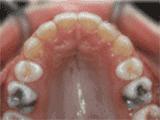

3、牙齿拥挤,个别牙异位,牙弓狭窄,导致局部牙齿重叠生长,两侧各拔牙一颗后,经过矫正是变成这样的~

4、牙列拥挤,前牙没有咬合,上下牙齿中线不对称,牙弓狭窄,上颌“*牙虎**”异位生长,经专业评估没有拔牙,经过矫正后的牙齿是这样的~